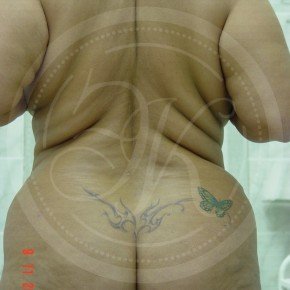

Фото до и после липосакции

В этой галерее мы публикуем снимки тех пациентов, которым была проведена липосакция. Фото до и после в полной мере позволяют оценить результат. Для каждого пациента мы подбираем тот вид вмешательства, который даст лучший результат при минимальном травматизме.